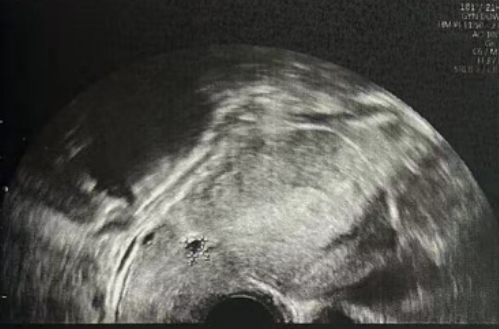

子宫内膜厚度:4.6 毫米,子宫有瘢痕大小 0.76*0.19 厘米

雌二醇:241 pg/mL

孕酮:0.13 ng/ml

子宫内膜厚度:9.3-10 毫米

- 有粘液滞留在腔内,从峡部瘢痕延伸至子宫底

- 双卵巢无囊肿

- 计划在胚胎移植前重复超声检查以冲洗峡部瘢痕

雌二醇:210.52 pg/mL

孕酮:0.3 ng/ml

子宫内膜厚度:8.9 毫米

微创清积液

在进行3毫升的子宫峡部切口冲洗后,经过经腹超声检查显示子宫内膜呈三线状,且子宫腔内未见液体。

• Pre-Irrigation灌洗前: